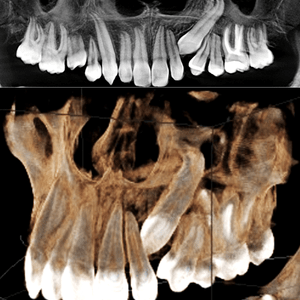

Scanner Cone-Beam CT de última generación

Panorámicas, teleradiografias y CBCT con el sensor más moderno, preciso y de baja dosis.